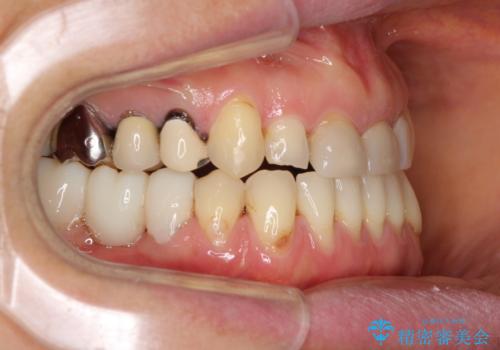

反対咬合や欠損を治療したい インビザライン矯正とオールセラミックブリッジ

虫歯治療や欠損補綴治療も必要でしたが、前歯が反対咬合であったので、セラミッククラウンやブリッジによる治療と並行して矯正治療を提案しました。

- 治療費の目安: 190万円(税込)費用は治療当時の料金となります

海外出張にとどまらず海外赴任もあり、途中2度の妊娠もあったため、治療には非常に長い期間を要することとなりました。